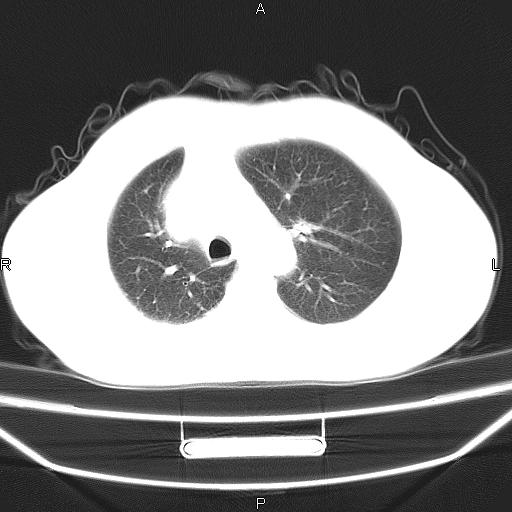

患者,男。50岁。近几日有咳嗽症状,无其他不适,既往病史无,考虑膈疝。请前辈们看看指导指导。

膈膨升,左下肺通气不良,膈肌好像还完整。

考虑左侧膈疝。

左侧膈疝。

符合隔膨升,膈肌较完整。